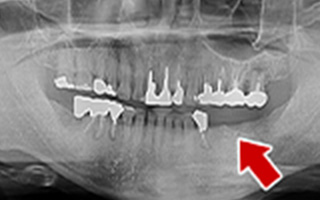

Before

After

| 60歳 男性 | 歯科大学病院 教授からの紹介 ご本人は産婦人科医 |

|---|---|

| 主訴 | 左下に歯が無くて食事がしずらい |

| 処置内容 | 2本インプラント埋入+再生処置 |

| 治療費用 | 下顎: 約80万円(税込) |

| 治療期間 | 下顎: 6ヶ月 |

| リスク | 術後の腫れ、痛み(ピークは3日後、1週間で軽減) |